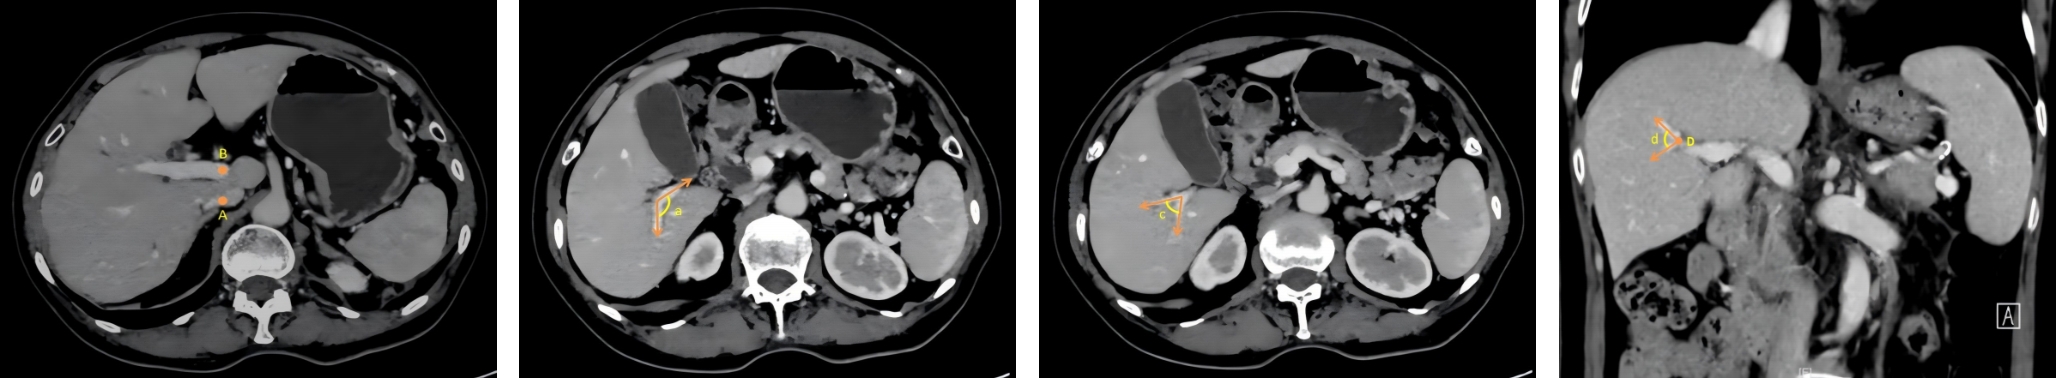

2026,35(1):124-140, DOI: 10.7659/j.issn.1005-6947.250635

Abstract:

Background and Aims The hepatic vascular and biliary systems exhibit substantial anatomical variability and complex spatial relationships, posing challenges for precise surgical planning based on conventional two-dimensional imaging. This study aimed to evaluate the clinical value of three-dimensional visualization in characterizing the spatial architecture of hepatic vasculature and bile ducts and to explore its association with hepatic volumetric distribution.Methods A total of 610 living liver donors and 158 patients with bile duct dilatation were retrospectively analyzed. Three-dimensional models of the hepatic artery, portal vein, hepatic veins, and bile ducts were reconstructed from contrast-enhanced CT images. Vascular and biliary anatomical patterns, spatial relationships, and their correlations with hepatic lobe and segmental volumes were systematically assessed.Results Three-dimensional visualization enabled intuitive and comprehensive depiction of hepatic vascular and biliary anatomy. Distinct portal vein configurations were associated with significant differences in regional liver volume distribution, with an increased proportion of the right posterior lobe observed in patients with specific portal vein branching patterns. The presence of an inferior right hepatic vein with a diameter ≥5 mm was also associated with a larger right posterior lobe volume. Analyses of extrahepatic and intrahepatic spatial relationships revealed relatively consistent positional patterns between the right hepatic artery, portal vein, and bile ducts, and a significant correlation was observed between the spatial courses of the right hepatic artery and the right posterior bile duct.Conclusion Three-dimensional visualization provides accurate preoperative assessment of hepatic vascular and biliary anatomy and clarifies complex spatial relationships and their volumetric implications. This technique offers critical anatomical support for precision hepatobiliary surgery and liver transplantation.